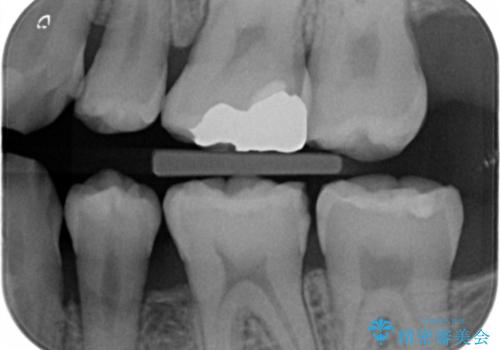

レントゲンや拡大鏡で確認をしたところ歯の表面は粗造になっていたが

う蝕があるわけではないので以下の提案を行った。

歯の表面が粗造なのは虫歯ではないが

歯の表面が溶けはじめて、虫歯になりやすい状態になっています。